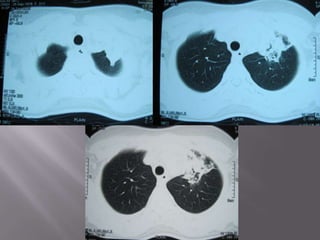

   Repeat chest X-Ray

   Suspicion shifted to the next accused:-

Lupus Pneumonitis

   Steroid dose hiked

   Fever disappears

   Cough subsides

   Chest pain subsides

   Chest X-Ray repeated after 1 week

   Pt discharged

   Repeat chest X-Ray @ 2 weeks follow-up